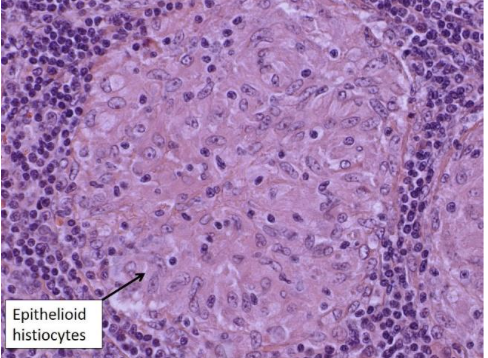

18

Granuloma = aggregate of ‘epithelioid’ histiocytes